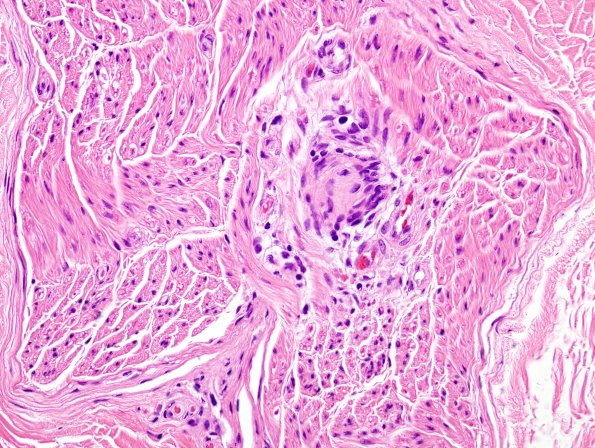

Multiple schwannomas within the endoneurium of spinal roots. (H&E)